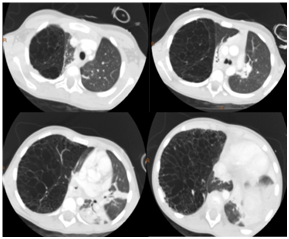

Figure 4 CT Chest lung windows.

Physical examination was notable for tachypnea with a maximal respiratory rate of 48 breaths per minute, tachycardia, pulse oximetry (SpO2) of 92%, diminished air exchange at right chest with asymmetric barrel chest (right > left) including increased anteroposterior diameter. Flexible fiberoptic bronchoscopy with bronchoalveolar lavage (FFB BAL) demonstrated mucoid impaction of the right mainstem bronchus causing ball-valve mechanism leading to air trapping with herniation of the right lung to the left. There was mucoid impaction within the right upper lobe (RUL) and right middle lobe (RML) bronchi, tracheobronchomalacia, particularly with the posterior distal trachea, and bronchomalacia of the right middle lobe bronchus and RUL bronchus. The mucosa of the tracheobronchial tree had diffuse inflammation. Airway clearance including beta-2 agonist were added to her inpatient treatment regimen, and further imaging obtained including chest CT with angiography (CTA) and ventilation-perfusion (V/Q) scan. The CTA revealed severe hyper expansion of the RML with multiple cysts that occupied the majority of her right hemithorax. The hyper expanded lobe was compressing atelectatic but otherwise normal appearing RUL and right lower lobe (RLL) parenchyma with severe mediastinal shift to the left. Lung V/Q scan showed minimal contribution by the right lung of only 11.3% with limited-to-no perfusion.